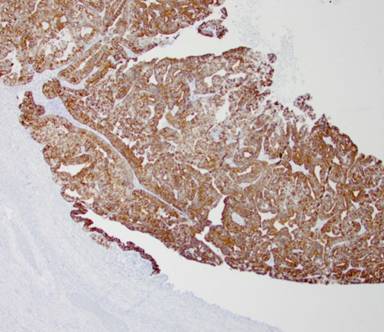

Secondary to her disease being potentially resectable, a diagnostic laparoscopy was performed to rule out extrahepatic disease. Biopsy of the segment 6 liver lesion demonstrated infiltrating glands staining diffusely for CK7, CK19, and CK20 consistent with a gallbladder primary (Figures 3 and 4). Concern was raised about the size of the left hemi-liver and the patient underwent portal vein embolization.

Figure 4. Original gallbladder primary with positive CK20 staining. |

The pathology specimen demonstrated a 10.0x6.5x0.5 cm papillary, pink, circumferential tumor located primarily in the body and neck of the gallbladder. Additional papillary areas that were non-contiguous with the main tumor were also identified in the body and fundus. The final cystic duct and liver margins were negative for any evidence of malignancy. Adenocarcinoma present in the liver resection specimen was morphologically identical to the gallbladder primary tumor (Figures 5 and 6). There was evidence of lympho-vascular invasion; however, no lymph nodes were identified in the sizable portal node dissection specimen. The patient underwent adjuvant chemotherapy with cisplatin and gemcitabine for six months and was followed by her local medical oncologist with tumor markers and serial imaging. Two years after her initial diagnosis, PET-CT showed a new 25x17 mm hypodense mass in the pancreatic head involving the main pancreatic duct causing mild upstream duct dilation and pancreatic parenchymal atrophy (Figure 7). There was no evidence of vascular invasion or biliary dilation on CT imaging. Endoscopic ultrasound showed a round hypoechoic mass in the inferior aspect of the pancreatic head and uncinate process measuring 23x21 mm in maximal cross section diameter. A fine needle aspirate (FNA) of the pancreas head mass demonstrated metastatic gallbladder carcinoma consistent with patient’s gallbladder primary.

Figure 6. Metastatic papillary gallbladder adenocarcinoma with positive CK20 staining. |